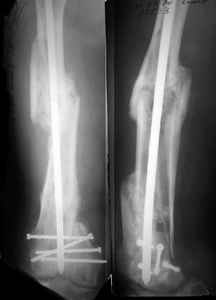

Attached are few examples from our Hospital:

A. Difficult reductions, even in retrograde nailing (my preference, easier control of "small" distal fragment) and it is much, much harder to do it anterograde (Alex, do you have one good case in your collection of anterograde nailing in very distal fractures - as you have suggested that I

should have done it in my previously posted case?

Malpositioning is much too common (recurvatum, varus - valgus).

B. Fixation loosening: distal cutting of the nail, non-unions do happen (cases attached).